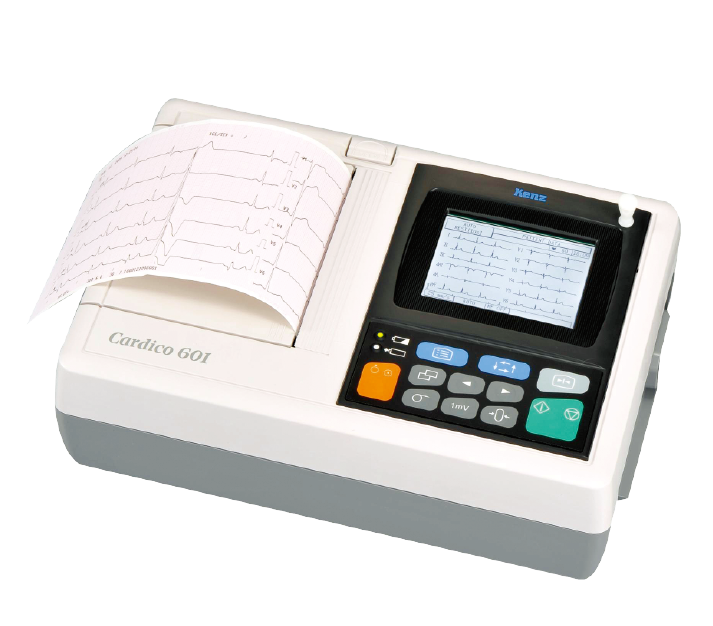

Portable ECG machine

ECG machine with six-channel digital automatic analysis, 12 lead synchronously display ECG wave type, which is suitable for outpatient, emergency, ward, physical examination and easy to carry.